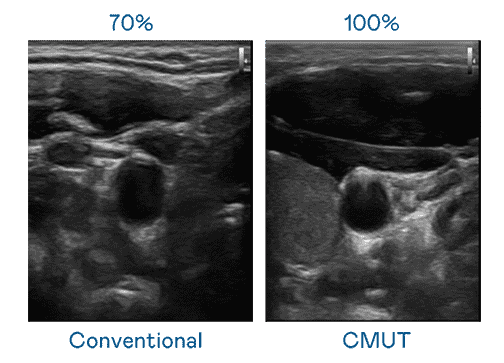

CMUT 技术是一种用电容式微机电元件来产生超音波讯号的技术。。与传统 PZT 压电式技术相比,,CMUT 频宽增加 30%,,,,更宽频的超音波讯号让影像解析度大幅提升,,,,是实现高影像品质医疗超音波扫描、、促进精准医疗发展的关键技术。。

超音波影像的解析度高低,,,首先取决于探头能发出的讯号频宽。。人生就是博 CMUT 可提供高清晰的超音波讯号,,,,提供高频宽、、、、高灵敏度、、、影像纹理细节更高的超音波影像,,,,协助医护人员缩短影像判读时间及利用精准的医疗影像进行诊断。。。